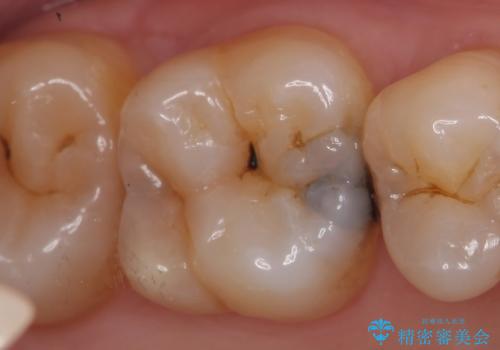

- 右上の奥歯で冷たいのもがしみるといらっしゃった方の症例です。

虫歯を除去後、セラミックインレーによる修復を行いました。